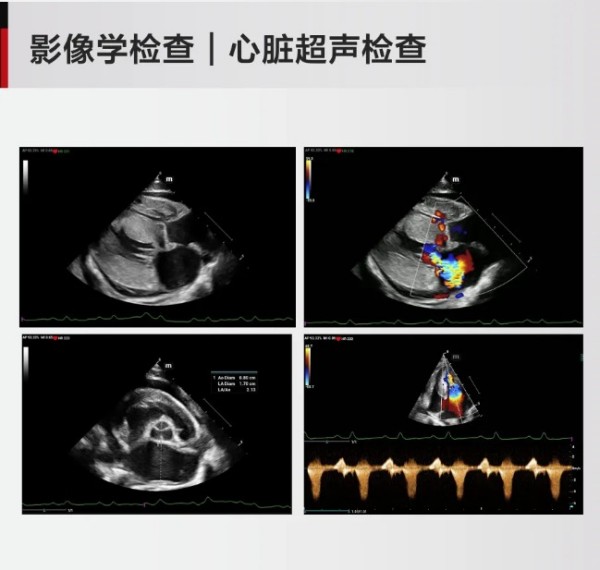

vetXpert 病例专栏|一例猫肥厚型心肌病的病例分析

来源:东西部小动物临床兽医师大会